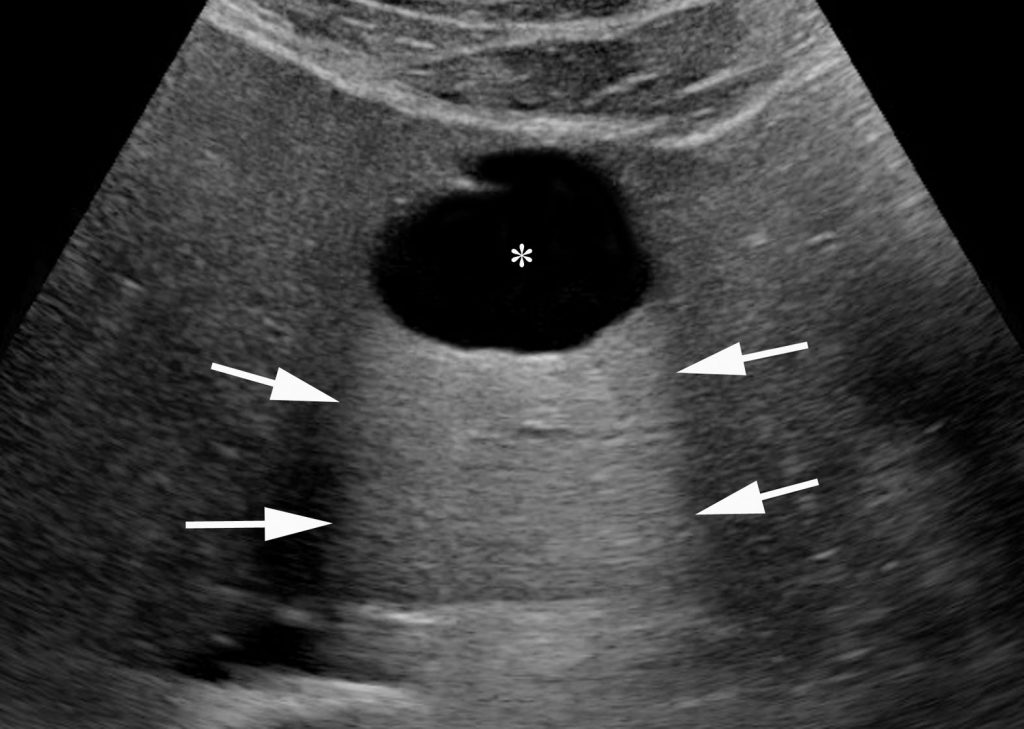

Ces kystes présentent toutes les caractéristiques des kystes simples :

- anéchogène avec un renforcement postérieur en échographie sans paroi ni cloison (figure 16.9) ;

Fig. 16.9. Image échographique de kyste hépatique typique réalisant un aspect strictement anéchogène (∗) avec renforcement postérieur (flèches) au sein du parenchyme hépatique.

Source : CERF, CNEBMN, 2022.

- de densité liquidienne en scanner ne se rehaussant pas après injection (figure 16.10) ;

La découverte d’un kyste simple d’aspect typique ne nécessite pas d’autre examen d’imagerie.